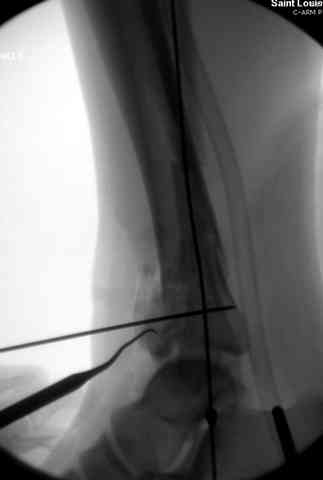

Снова приветствую вас, коллеги. К моменту вступления в обсуждение аксакалов, операция была, увы, выполнена(31.10.07.) Начали с доступа к наружной лодыжке, произвели ее фиксацию спицами, развернули кусок заднего края, наложили дистрактор, затем произвели дистракцию, фиксацию спицами дистального эпиметафиза б/бк,Рентгено-контроль. синтез наружной лодыжки 1/3пластиной. из двух коротких разрезов сформирован канал под медиальную тибиальную пластину LCP. Края ран ушиты без натяжения. Прочувствовать жесткость фиксации винтами с угловой стабильностью не удалось, поэтому дистрактор оставлен на энное время.

На представленных R-снимках не окончательный вид после остеосинтеза. Дистальная опора давила на стопу, пришлось ее сместить проксимально, в рез-те чего, она закрыла щель сустава, последние снимки не информативны.